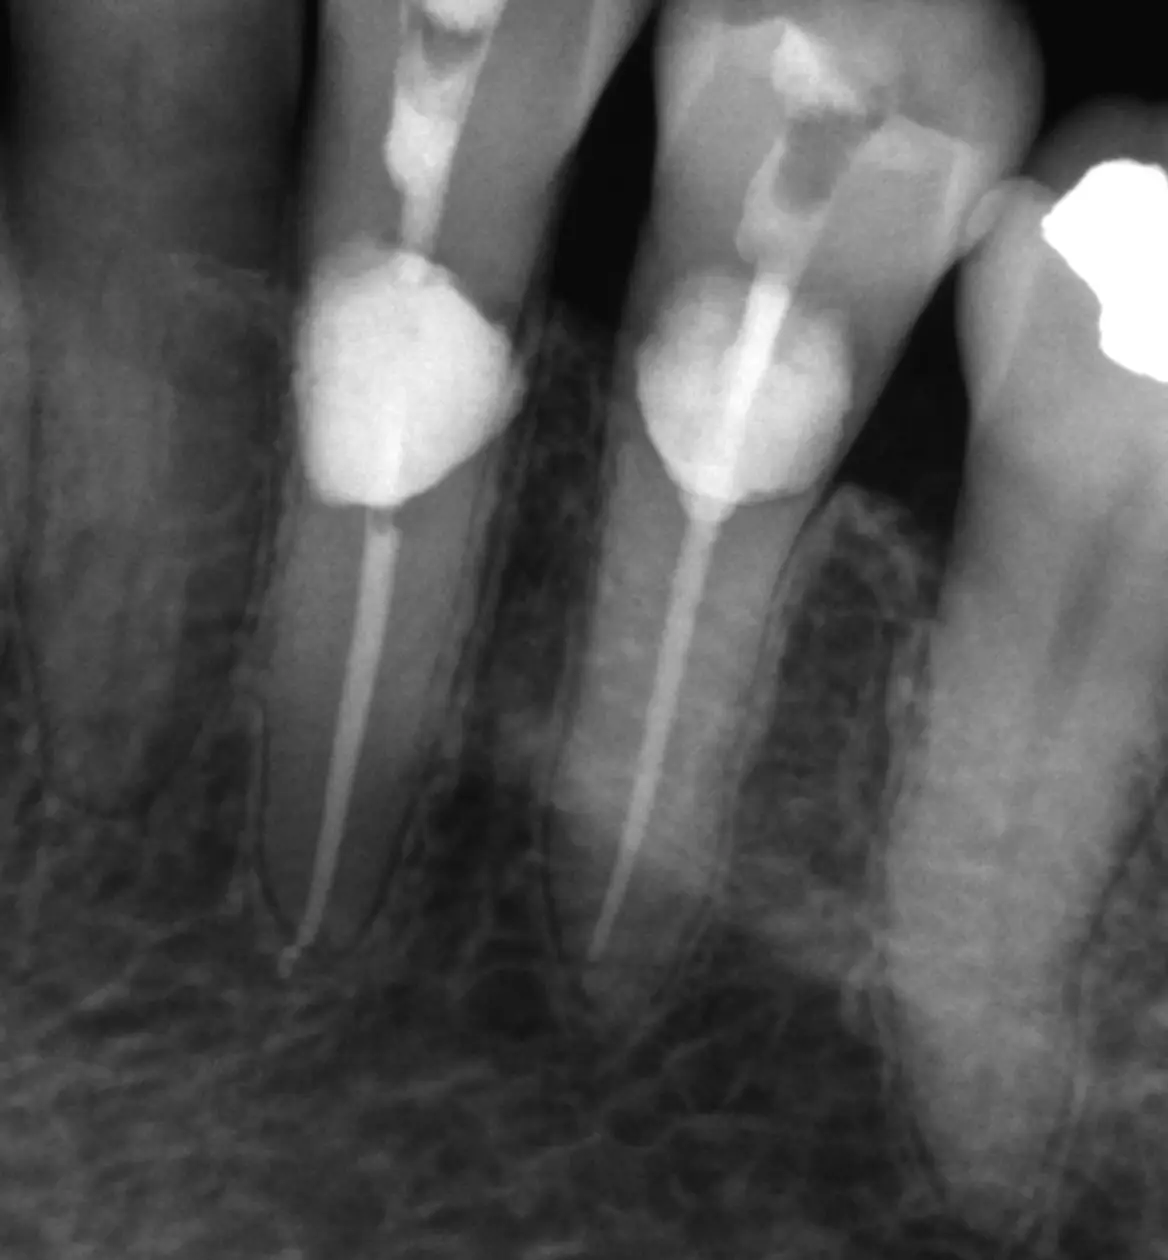

Successful Root Amputation